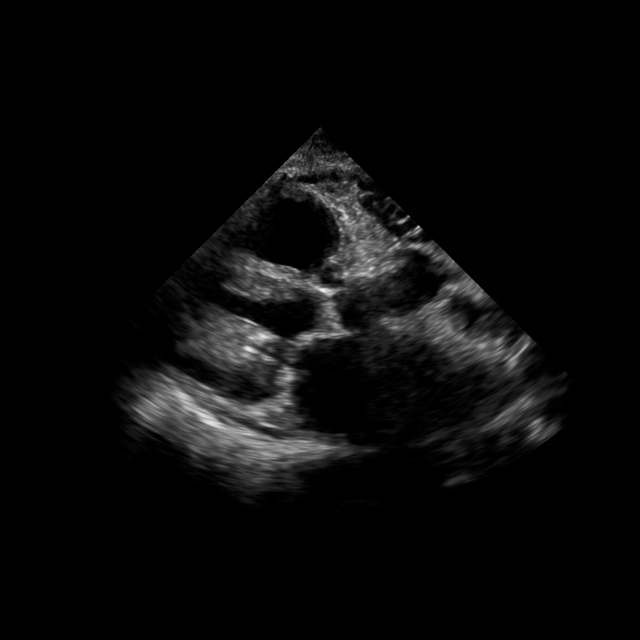

Interactive segmentation

We adapt EchoVLM for chamber segmentation tasks by attaching a prompt-based (box) encoder-decoder module following SAM (kirillov2023segment). Training and evaluation is conducted on three public benchmarks: EchoNet-Dynamic (left ventricle masks in A4C views) (ouyang2020echonetdynamic), EchoNet-Pediatric (left ventricle masks in A4C, PSAX views) (reddy2023video) and CAMUS (left ventricle and atrium masks in A2C views) (leclerc2019deep). We report Dice similarity coefficient (DSC) and compare with task-specific baselines (U-Net (ronneberger2015u) or Deeplabv3 (chen2017rethinking)), MedSAM (ma2024segment) and the vision FM EchoApex (echoapex2024).

EchoVLM outperforms tasks-specialists and achieves similar performance as vision FM. EchoVLM attains the best DSC on EchoNet-Dynamic (93.1%) and EchoNet-Pediatric-A4C (92.4%), and ties EchoApex on EchoNet-Pediatric-PSAX (93.0%) (Table 3). On the CAMUS dataset, EchoVLM matches EchoApex for left ventricular segmentation (93.8%) and achieves competitive performance for left atrial segmentation (90.2%). Visualization of segmentation results on CAMUS using EchoVLM is shown in Figure 7. These results indicate that our pretraining maintains transferable local features for segmentation across datasets.

We benchmark chamber segmentation on three public echocardiography datasets: EchoNet-Dynamic (ouyang2020echonetdynamic), EchoNet-Pediatric (echonetpediatric2021), and CAMUS (leclerc2019deep). These datasets span different populations and acquisition protocols, providing complementary challenges for evaluation. EchoNet-Dynamic contains over 10k apical four-chamber (A4C) videos with end-diastolic (ED) and end-systolic (ES) left ventricle masks. EchoNet-Pediatric comprises pediatric A4C and parasternal short-axis (PSAX) videos with left ventricle annotations. CAMUS provides 500 adult patients with A2C and A4C views annotated for both left ventricle and left atrium at ED/ES. Dataset statistics are summarized in Table 11.

We adapt EchoVLM for interactive segmentation by attaching a prompt-conditioned encoder–decoder following SAM (kirillov2023segment). Models are trained with DiceCE loss and evaluated using the Dice similarity coefficient (DSC). As shown in Table 12, EchoVLM consistently outperforms task-specific baselines (U-Net, MedSAM) and performs on par with the vision foundation model EchoApex across all datasets. Notably, EchoVLM achieves the highest DSC on EchoNet-Dynamic (93.1%) and EchoNet-Pediatric A4C (92.4%), while matching EchoApex on EchoNet-Pediatric PSAX and CAMUS. These results indicate that measurement-grounded multimodal pretraining preserves fine-grained local features required for precise structure segmentation, while also transferring across age groups and acquisition settings.